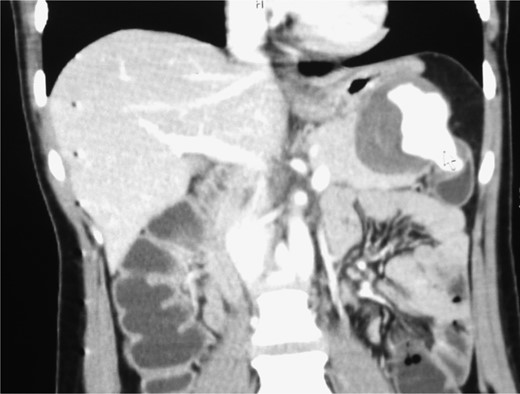

A triphasic, contrast enhanced computed tomography (CT) scan revealed a 6 cm × 5.2 cm well defined, heterogeneous, hypodense mass arising from the pancreatic tail, with an extremely enhancing component (200 Hounsfield units) on its lateral side, a feeder vessel arising from the splenic artery and a small splenic infarct (Fig. 1). Fascial margins of the mass were poorly defined from the splenic hilum and splenic flexure of the large intestine (Fig. 2). CT imaging was supportive of a differential diagnosis of a solid pseudopapillary tumor of the tail of the pancreas with invasion of the colonic wall and compression of the stomach.

CT shows the point of communication (free rupture) between the aneurysm and splenic flexure of the colon.